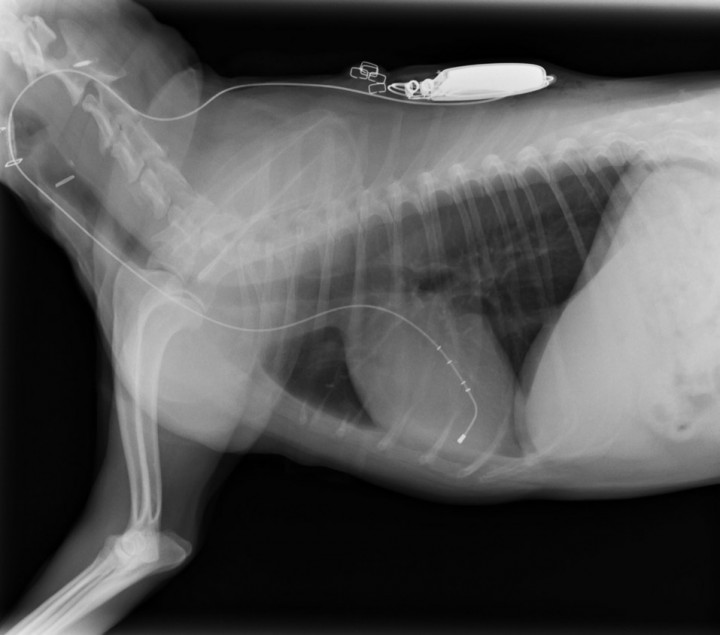

Durante el postquirúrgico el paciente es controlado mediante estudio radiográfico del tórax, electrocardiograma y ecocardiografía. El estudio radiográfico del tórax a las 24 horas postintervención revela la resolución del edema pulmonar, así como una disminución del índice vertebral a 11 cuerpos vertebrales (Fig. 6). Por su parte, el control electrocardiográfico muestra una frecuencia ventricular de 100 lpm (Fig. 7).

<p>Se observa una disminución en el tamaño de la silueta cardiaca (medición de índice de Buchanan), con una correcta colocación del electrodo ventricular derecho.</p>

Figura 6

Se observa una disminución en el tamaño de la silueta cardiaca (medición de índice de Buchanan), con una correcta colocación del electrodo ventricular derecho.